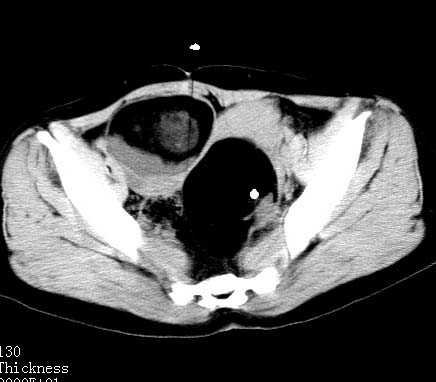

女性 病人 44岁 盆腔 下腹部痛1天!

盆腔内低密度为主混杂等密度及少许囊样与班状钙化影,如果做了肠道准备就好了。支持畸胎瘤。当然做mri会更好

典型的双侧附件畸胎瘤.

支持各位大侠观点.病人有急性腹痛,需除外有扭转可能.建议mri.

盆腔多发畸胎瘤,较为典型。